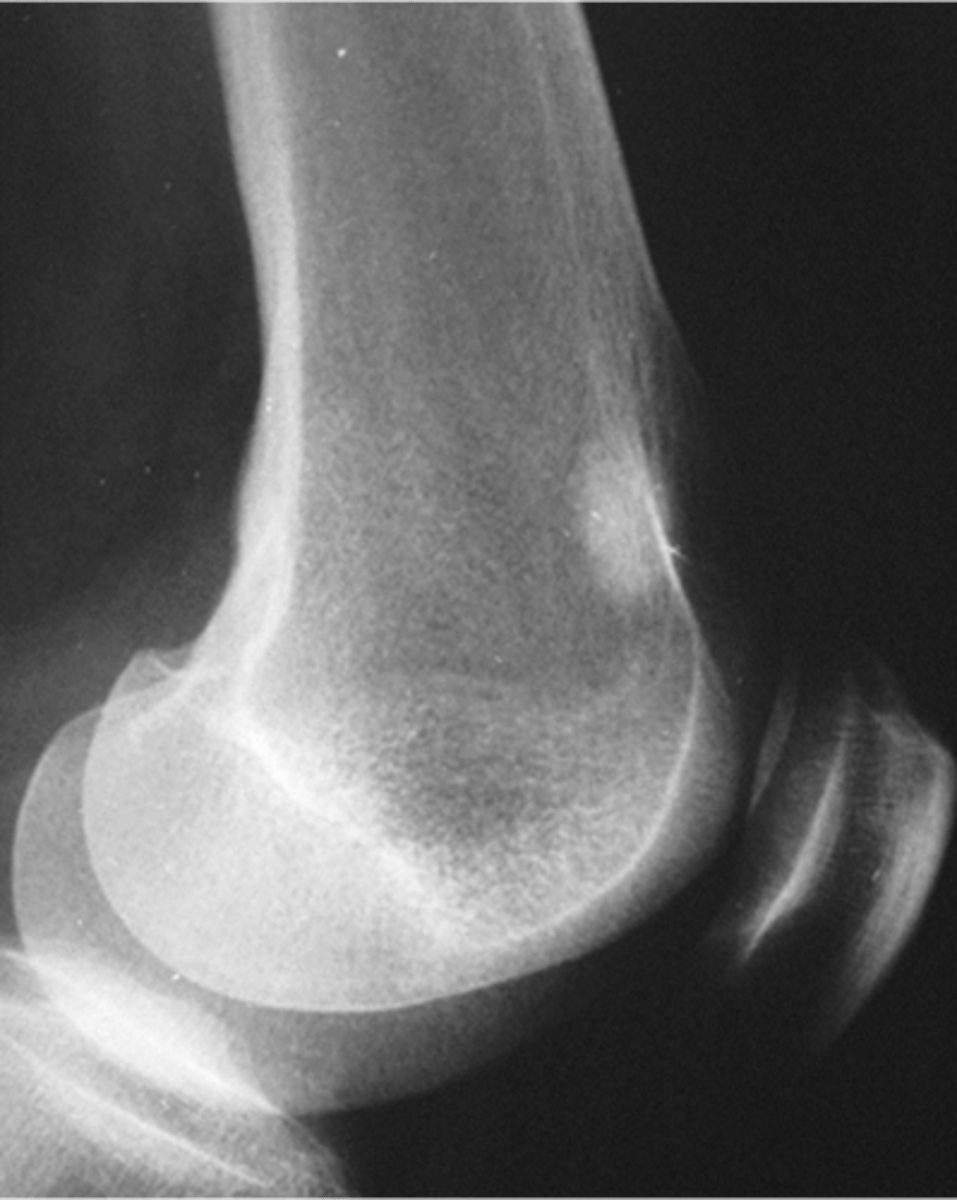

Sessile

_____ solitary osteochondroma:

- Broad-based

- Metaphyseal

- Wide, broad metaphysis

- Lucent when en face (on end)

- Cartilage cap uncommon

<p>_____ solitary osteochondroma:</p><p>- Broad-based</p><p>- Metaphyseal</p><p>- Wide, broad metaphysis</p><p>- Lucent when en face (on end)</p><p>- Cartilage cap uncommon</p>

New cards

Cartilage cap

What is this?

<p>What is this?</p>